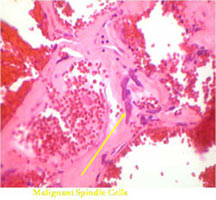

- Thin septae exist between the cystic cavities that harbor malignant appearing spindle cells producing scant osteoid

- Septa composed of atypical, bizarre, malignant appearing spindle cells with atypical nuclei and atypical mitotic figures

- Osteoid production is scant, focal and lace-like

- Telangiectatic osteosarcoma has bizarre, atypical malignant cells and scant, lace-like osteoid